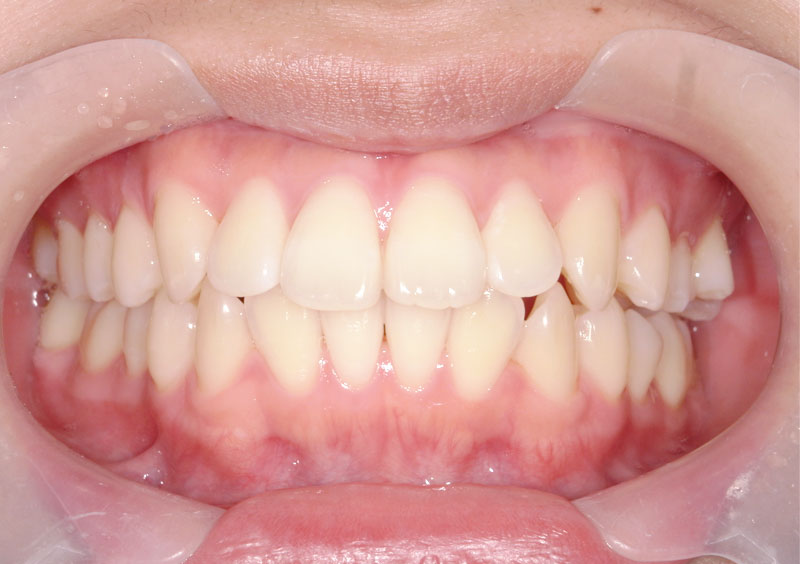

症例02

治療前

治療中

治療後

主訴 | 前歯がガタガタ、 スペース不足で今後が不安。 |

治療期間 | 2年間 |

治療費 | ¥190,000(税込) |

治療内容 | 上下顎に床矯正装置を使用。 上顎のみ、装置を追加し、 合計3装置使用。 |

治療のリスク | 小学校低学年での治療開始であり、 装置の使用、管理にリスクがあったが 本人、家族の協力もあり予定期間での 改善が得られた。 |